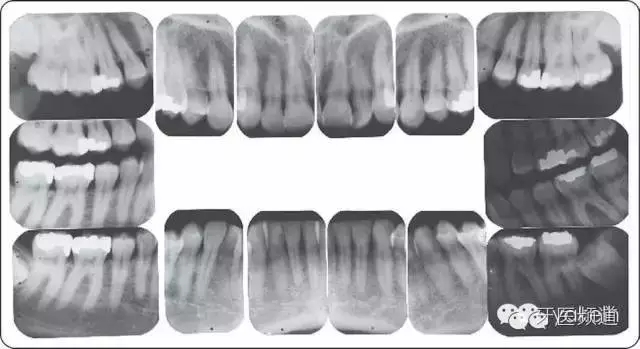

全口根尖片顯示(圖5~圖7):

● 沒有鄰面骨喪失。

● 充填體邊緣缺損。

● #19根分叉約20%骨喪失,與其他牙齒根分叉區(qū)比較,骨質(zhì)密度減低(透射影)。

● #19近遠(yuǎn)中根尖周透射影。

● 第三磨牙阻生。

● 無齲齒。

圖5 全口牙齒根尖片。